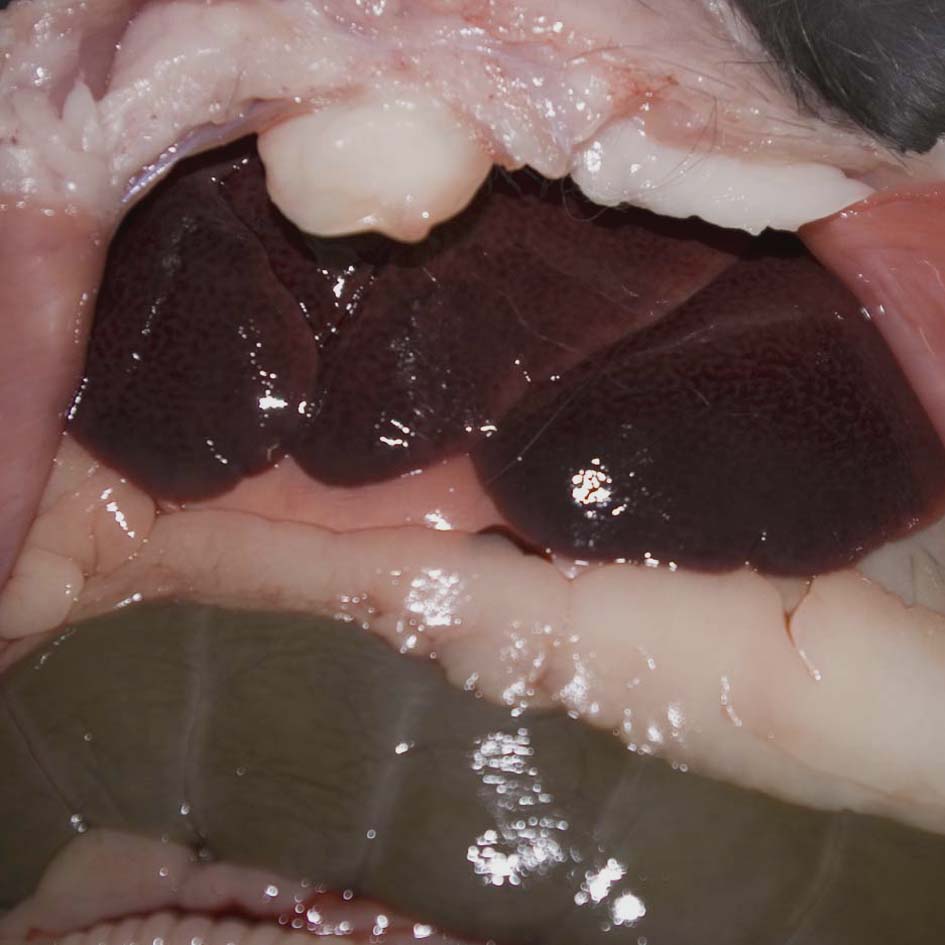

Enlarged congested liver

An enlarged congested liver can be due to rabbit haemorrhagic disease (RHD) but is also a macroscopic feature of other conditions, such as congestive heart failure or septicaemia. Close inspection of the liver shows a mottled appearance, which is suggestive of RHD. In this case, RHD was diagnosed from the histopathological finding of characteristic hepatocellular necrosis.